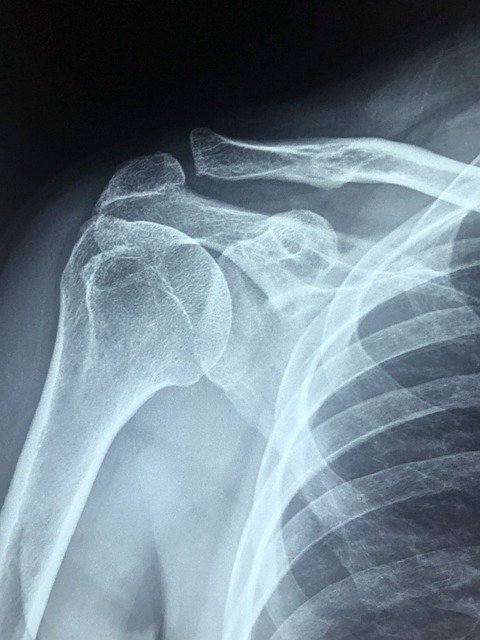

어깨 통증은 위에 설명드린 것처럼 여러 가지 요인으로 인해서 생기지만 원인은 어깨 관절에 이상이 생긴 경우 또는 어깨에 있는 근육이나 신경에 염증이 생긴 경우 무리한 운동으로 근육이 파열되거나 근육통이 생긴 경우 어깨 통증을 호소하는 경우가 있습니다.

오십견:40~50대에 자주 발생하는 질환으로 알려진 오십견은 주로 노화로 인해 발생되는데. 나이를 먹어가면서 점차 관절에 있는 연골이 닳게 되어서 통증이 생기거나 관절낭이 염증을 일으켜 유발하는 질환입니다. 오십견의 경우 어깨 관절이 뻣뻣해 지거나 팔을 들어 올릴 때 또는 고개를 돌릴 때 통증을 유발하기도 합니다. 요즘에는 젊은 사람들에게서도 나타나는 질환이기 때문에 젊다고 해서 오십견이 생기지 않는다고는 할 수 없습니다.

석회화 건염:명확하게 밝혀진 원인은 없지만 노화로 인해서 생기거나 힘줄에 손상이 생겨 염증이 생기거나 자극이 지속되는 경우 발생하기도 한다 합니다. 어깨 관절에 석회가 끼어 염을 유발하고 극심한 통증이 발생시키는 질환입니다. 어깨를 누르면 극심한 고통을 느끼며 팔을 들어 올리기 힘들어진다고 합니다. 어떤 사람은 통증이 있는 어깨를 누르면 테이저건에 맞은 것처럼 아프다고 말했습니다.

어깨 충돌증후군:어깨를 주로 많이 사용하는 직업을 가진 사람들에게 많이 발생하는 질환으로 알려져 있는 어깨 충돌증후군은 50대 이상의 중장년층에게서도 많이 발생합니다. 노화로 인해서 어깨가 많이 약해진 경우에도 이질환이 발생하는데 통증이 심하기 때문에 팔을 들어 올리는 것이 힘들고 심각한 경우에는 통증으로 인해서 잠을 자지 못할 정도로 힘들다고 합니다. 어깨 충돌 증후군은 대부분 약물치료와 운동치료를 통해서 치료하는 것이 일반적입니다.

회전근개 파열:어깨를 움직일 때마다 사용되는 근육과 힘줄로 이루어진 회전근개가 운동이나 충격으로 인해서 파열되어 염증이 생긴 경우 통증을 유발할 수 있으며 또는 노화로 인해서 회전근개가 파열되는 경우에 발생하는데 증상은 팔을 높이 들어 올리면 통증이 생기고 팔을 움직일 때마다 어깨 부위에서 소리가 난다면 회전근개 파열 일수 있습니다.